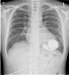

Abbildung 2: LVAD-Patient LVAD-Patient beim Golf spielen |